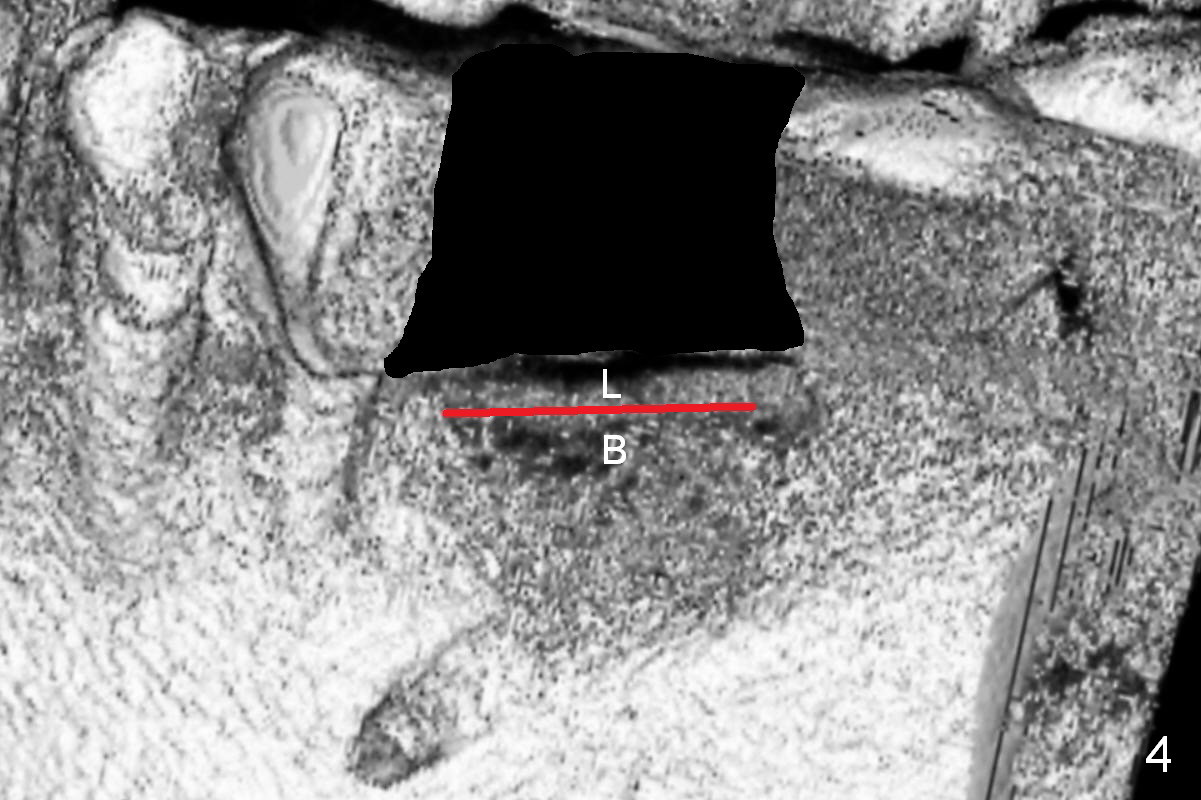

Bone density at the crest appears to be low (Fig.3 arrowheads). After pontic removal (Fig.4 black area) and incision, use #15 scalpel, bone scalpels and bone blades to start bone expansion (red line). Bone expansion continues with D osteotomes (Fig.5 red area) which mainly moves the buccal plate (B) buccally. The 3rd step of bone expansion is to use RT (round tapered) osteotomes or bone expanders (Fig.6 white circle); the buccal plate keeps being expanded more the lingual one (L). When an implant is placed, the lateral spaces created by expansion will be filled with bone graft. If the depth of osteotomy is not enough, use drills to reach the desired one.